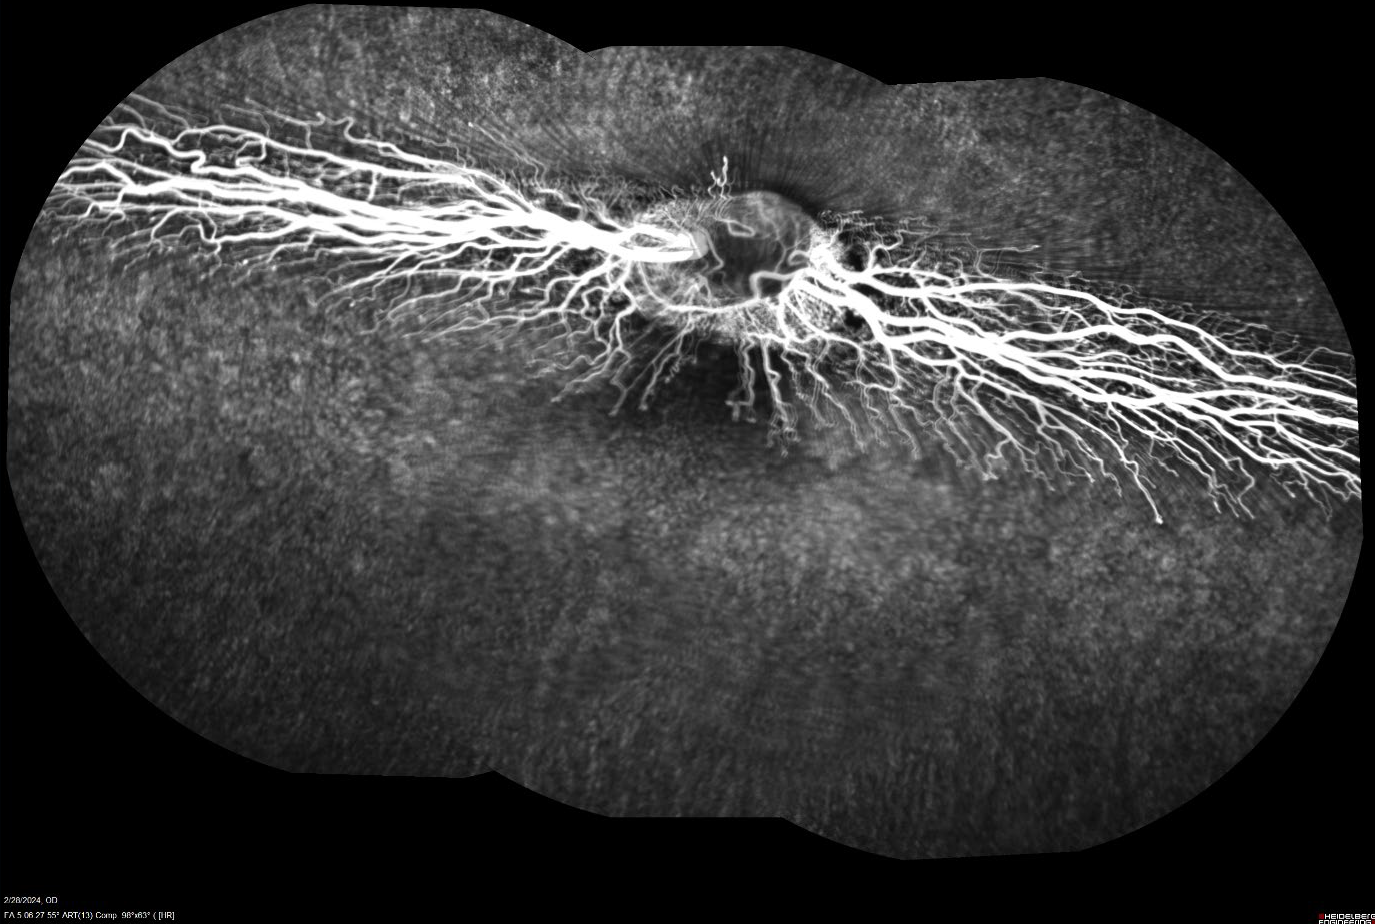

• The confocal laser scanning ophthalmoscopy (cSLO) capability of the Heidelberg Spectralis HRA+OCT utilizes the tissue penetration and reflectance characteristics of multiple wavelengths to generate high-contrast fundic images. Additionally, through the use of the blue autofluorescence (BAF) and indocyanine green angiography (ICGA) settings, the scientists at GD3 can provide assessments that reveal the angiographic characteristics of the retinal and choroidal vasculature. Through the collection of real-time video recordings during and after fluorescein injection with our advanced fluorescein angiography (FA) procedure, these data can provide the information needed to assess the safety and efficacy of a variety of ocular disease models and therapeutics.

Figure 4. Composite fluorescein angiography (FA) image of a rabbit retina post-fluorescein injection.